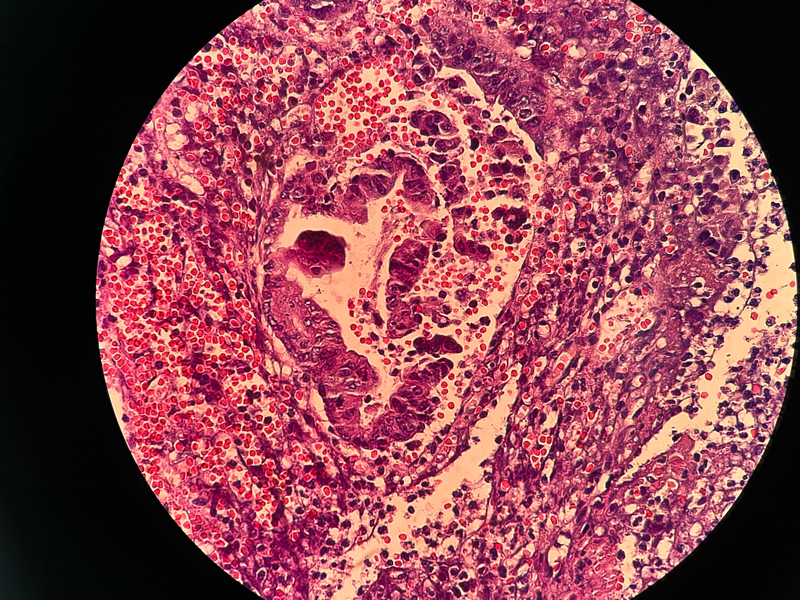

性别

女

年龄

54

临床诊断

急性阑尾炎

一般病史

持续性右下腹痛8小时

标本名称

阑尾

大体所见

阑尾约7.1cm ,直径约1.0-1.2,局部有脓苔

请各位老师看下这有没有问题,担心漏诊

化脓性阑尾炎。